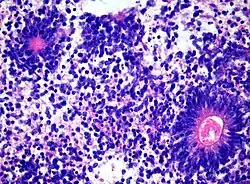

Medulloepithelioma, on the other hand, are tumors involving the constant cell division on the epithelium tissue where bundle of neuron endings are located.[1] Such tissue will differentiate into a similar form as the embryonic neural tube, also known as the starting structure of the central nervous system.[1][2][3] Medulloepitheliomas also present a pattern known as rosettes, characterized by the arrangement of a bundle of cells into circular shapes and around a center or a neuropil.[1] Ependymoblastoma also present rosettes as well as a higher density of cells.[1][3] It involves the process of differentiation into ependymal cells.[2][3]

Rosettes in Ependymoblastoma histology